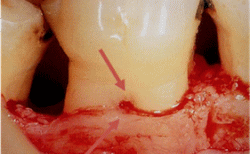

根分岐部でのSRP(歯石除去)の困難度

![]() |

7mm 以上のポケットの根分岐部は、完全な除去は困難 |